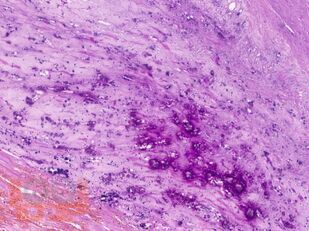

В учебном пособии представлен теоретический материал, перечень макропрепаратов и микропрепаратов, демонстрирующих типовые проявления патологических процессов. В цветных иллюстрациях и в описании микропрепаратов сделан акцент на наиболее важных гистологических изменениях, позволяющих на светооптическом уровне диагностировать и дифференцировать состояния, отклоняющиеся от нормы, в том числе с использованием различных гистологических окрасок. Пособие помогает выделить главные аспекты изучаемых патологических процессов, организовать и конкретизировать учебный процесс.